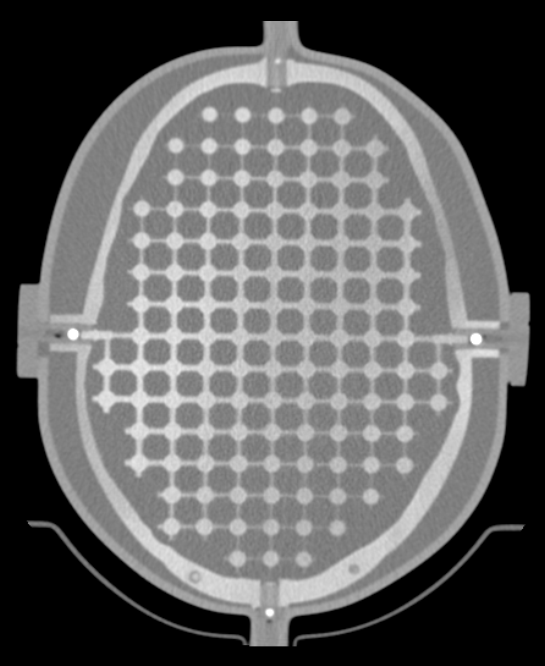

Finely Detailed Inter-Cranial 3D Design

The entire inter-cranial portion of the skull volume is filled with an orthogonal 3D grid of 2.5 mm diameter cross-like shaped rods spaced 10 mm (I-S), 10.5 mm (AP), and 11 mm (L-R). Extra material added in the grid intersections increases grid signal. Five extended axis-rods intersect at the reference origin of the grid. The end of each extended axis is fitted with CT/MR markers allowing for accurate positioning with lasers and co-registration of CT and MR image sets.

The phantom contains air voids on both sides that replicate ear canals. These voids are utilized to assess common distortions encountered in clinical settings.

The SRS MR Distortion Phantom can be imaged using X-ray, CT and MR. It images well with all MRI sequences tested to date, including T1 weighted, T2 weighted, 3D Time of Flight, MPRAGE and CISS.